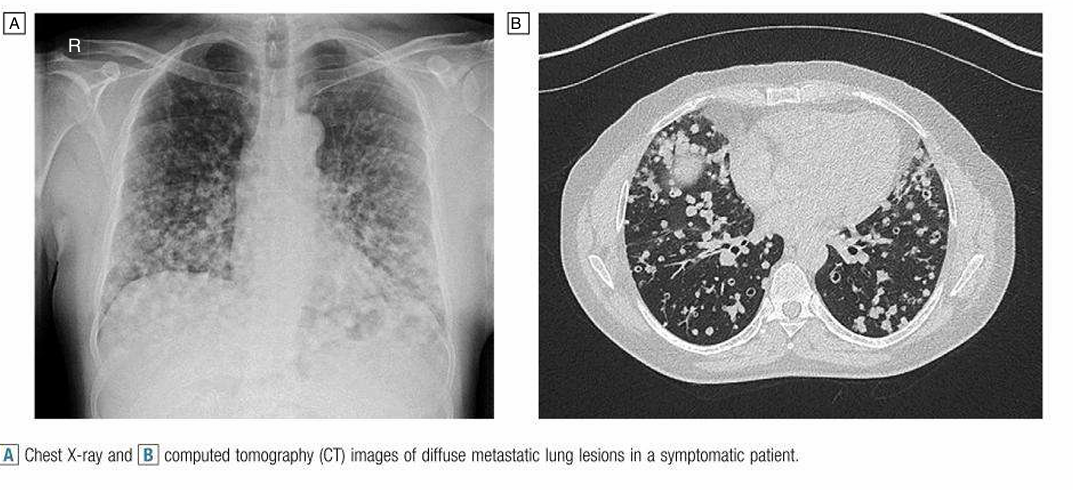

Lung metastases are common in breast cancer, colon cancer, renal cancer, sarcoma and tumours of the head and neck. The presentation is usually with a lesion on chest X-ray or CT. Solitary lesions require investigation, as single metastases can be difficult to distinguish from a primary lung tumour. Patients with two or more pulmonary nodules can be assumed to have metastases. The approach to treatment depends on the extent of disease in the lung and elsewhere. For solitary lesions, surgery should be considered, with a generous wedge resection, or radiofrequency ablation if available. Radiotherapy and systemic anti-cancer therapies can be used, dependent on the underlying primary cancer diagnosis (Fig. 1).